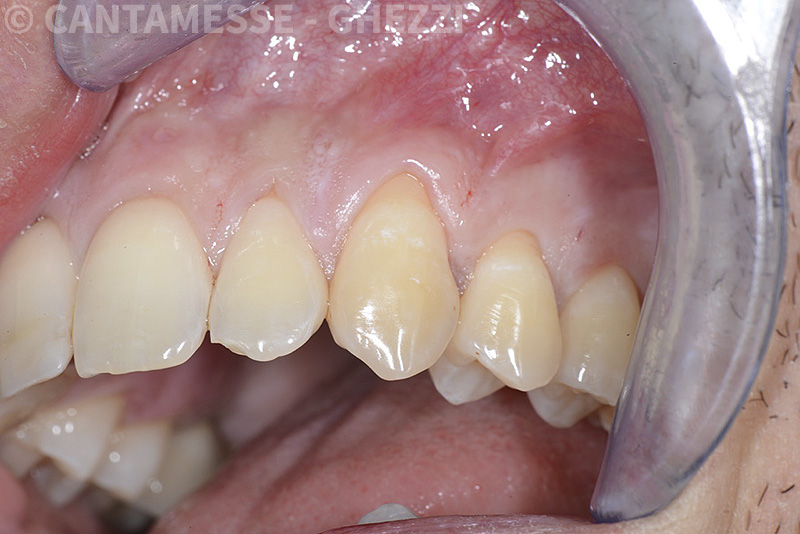

Vengono utilizzati 2 tipi di provvisori: il primo, cementato ai denti vicini, viene utilizzato dal momento dell’estrazione del dente fino ad impianto osteointegrato (circa 6 mesi); il secondo, avvitato direttamente all’impianto, ha una funzione di prova estetica ma soprattutto di guida per la maturazione dei tessuti gengivali peri-implantari portandoli verso la maturazione completa prima di posizionare la corona finale in disilicato di litio.